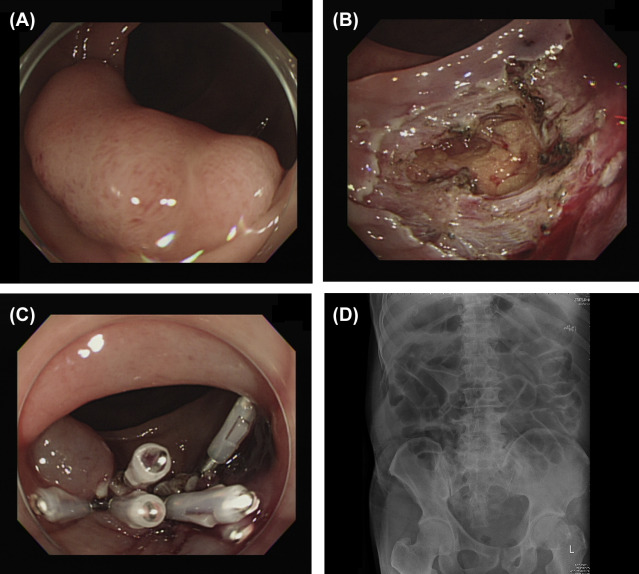

Histopathology revealed adenoma with low-grade dysplasia (n  = 18), adenoma with high-grade dysplasia (n  = 7), and adenocarcinoma (n  = 8). None of these patients had recurrence in follow-up colonoscopy, with the longest follow-up period being 1125 days and the shortest being 92 days. However, two patients, including the one with piecemeal resection, did not receive follow-up colonoscopy at our hospital. Perforations occurred in two patients who underwent ESD, which were successfully closed with endoscopic hemoclips ( Fig. 2 ). These patients were hospitalized without oral feeding for 3 days and 5 days, respectively, and given broad-spectrum antibiotics with close monitoring for possible leakages. Another three patients were found to have pneumoperitoneum after the procedure but without any peritoneal signs, and they were observed for a few days in our hospital. All five patients were discharged smoothly without other complications.

Endoscopic submucosal dissection (ESD) perforation. (A) A laterally spreading ...

Figure 2.

Endoscopic submucosal dissection (ESD) perforation. (A) A laterally spreading tumor about 3.0 cm in size in the transverse colon. (B) Perforation of about 2 cm with the omentum underneath identified after ESD. (C) Hole sealed with endoscopic hemoclips. (D) No free air was found on radiography after ESD.